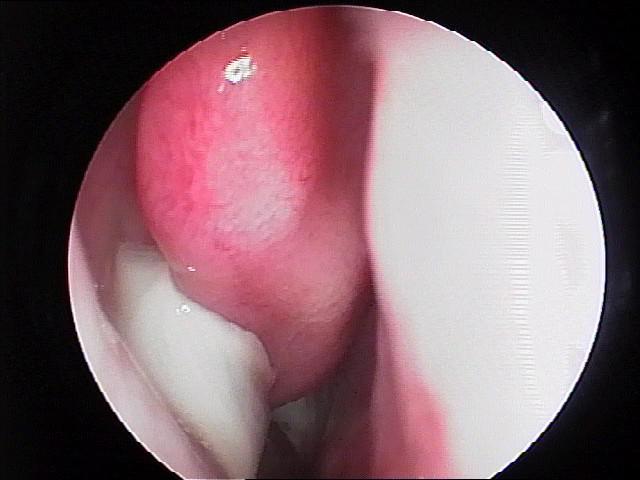

3、手术治疗:①鼻窦内窥镜手术,即利用光导纤维成像,有直观清晰、准确、导光率高的特点,配合专门的手术器械,明显提高手术的精确度,损伤小、针对性强,病变去除彻底,并发症少,预后好,复发率明显降低。鼻窦内窥镜手术需住院治疗。②辅助手术,为了达到鼻内镜鼻窦手术的效果,就需在清除病变的同时针对不同的病人做一些辅助手术,其中包括切除解剖变的中鼻甲,摘除中鼻道的息肉,咬除膨大的筛泡,纠正高位鼻中隔偏曲,部分下鼻甲切除等。这些手术看似与鼻窦手术无关,但可直接影响手术疗效,患者应对此有正确的认识,不要认为是医生额外增加的手术。